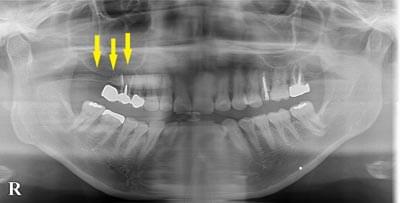

患者様の治療前のレントゲン写真です。写真の黄色矢印部の歯の周囲は、重度の歯周病で大きく歯槽骨が吸収されてしまっていました。そのため、写真の、赤色矢印で示す、下顎骨の中を通る神経までの距離がなく、インプラント埋入には、骨の高さが不足していました。

骨移植による骨造成について

重度の歯周病の歯を抜歯して、インプラント治療を行う予定となりました。